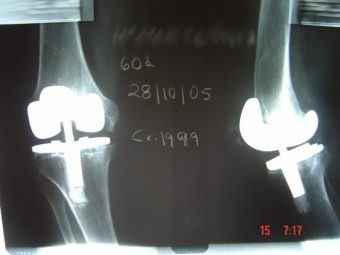

Revisión de prótesis de rodilla

Envíado por Dr. Ricardo Antonio Gómez G.